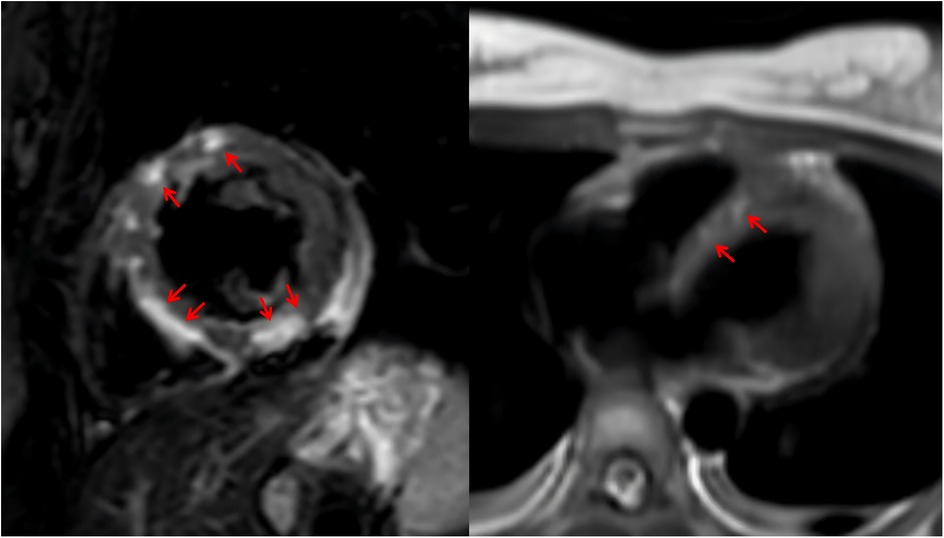

Given the onset of AKI, CRRT was initiated immediately upon the patient's arrival in the emergency intensive care unit (EICU) to manage fluid overload, correct severe metabolic acidosis, and remove inflammatory mediators. The CRRT modality selected was continuous venovenous hemofiltration (CVVH). Upon admission, continuous cardiac monitoring revealed frequent episodes of supraventricular tachycardia. After hemodynamic stabilization, a low-dose esmolol infusion was administered to control the heart rate. Initial thyroid function tests showed the following results: triiodothyronine (T3) 5.49 ng/ml, free triiodothyronine (FT3) >20.00 pg/ml, thyroxine (T4) 15.78 μg/dl, free thyroxine (FT4) >5.00 ng/dl, and thyroid-stimulating hormone (TSH) 0.070 μIU/ml. The patient exhibited elevated FT3 and FT4 levels, based on both the Japan Thyroid Association (JTA) guidelines for the management of thyroid storm and the Burch-Wartofsky Point Scale (65 points), these findings are consistent with a diagnosis of TS (7). A review of the relevant literature indicated that CRRT could be utilized in the acute phase management of TS (8). The CRRT modality was not adjusted. Consequently, the decision was made to continue CRRT, with its efficacy being assessed through serial monitoring of thyroid hormone levels. By day 3, thyroid hormone levels significantly decreased (Table 1). By day 5, LVEF improved to 57%, and no ventricular arrhythmias were observed. Unfortunately, both the ultrasonography and ECG were performed at the bedside using mobile devices. Due to a routine memory update of the equipment, the corresponding imaging data were not saved. VA-ECMO was successfully weaned. By day 6, methimazole was added to manage hyperthyroidism. After 3 weeks of treatment, the patient was successfully transferred to the general ward and underwent cardiac MRI, which revealed multifocal myocardial edema involving the left ventricular interventricular septum, anterior wall, and inferior wall (Figure 2). After 36 days of systematic treatment, the patient was successfully discharged with complete renal function recovery (no longer requiring renal replacement therapy) and satisfactory neurological recovery, demonstrating full independence in daily activities and achieving an optimal clinical outcome. Figure 3 is a timeline of the clinical condition progress and major management of the patient.

Figure 2

MRI scans showing heart tissue with red arrows indicating areas of interest. The left image is a cross-sectional view with several arrows pointing to the heart's periphery. The right image presents a horizontal view with two arrows highlighting specific regions.

Figure 2. The patient's MRI.